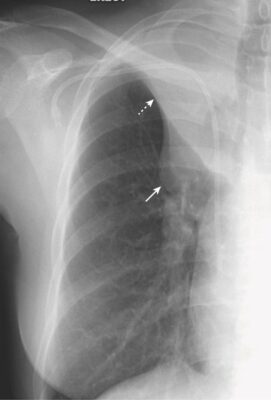

Xẹp phổi thùy dưới (Hình 12, A và Hình 12, B)

- Trên phim X quang thẳng:

- Cả thùy dưới bên phải và bên trái xẹp xuống tạo thành mật độ hình tam giác kéo dài từ đỉnh của rốn phổi đến đáy của nó ở phần trong của nửa cơ hoành bị ảnh hưởng.

- Có sự nâng lên của nửa cơ hoành ở bên bị ảnh hưởng.

- Tim có thể lệch về phía mất thể tích.

- Có sự dịch chuyển xuống dưới của rãnh liên thùy lớn (xem Hình 12, C).

- Trên phim X quang nghiêng:

- Có cả sự dịch chuyển xuống dưới và ra sau của rãnh liên thùy lớn cho đến khi thùy dưới bị xẹp hoàn toàn tạo thành mật độ hình tam giác nhỏ ở góc sườn hoành sau (xem Hình 12, B).

- Ở bệnh nhân nặng, xẹp phổi thường xảy ra nhất ở thùy dưới bên trái.

- Luôn kiểm tra nửa cơ hoành trái để chắc chắn rằng có thể quan sát được toàn bộ cơ hoành trái qua bóng tim vì xẹp phổi thùy dưới bên trái sẽ biểu hiện bằng sự biến mất (bóng bờ) của toàn bộ hoặc một phần của cơ hoành trái (xem Hình 12, A) .